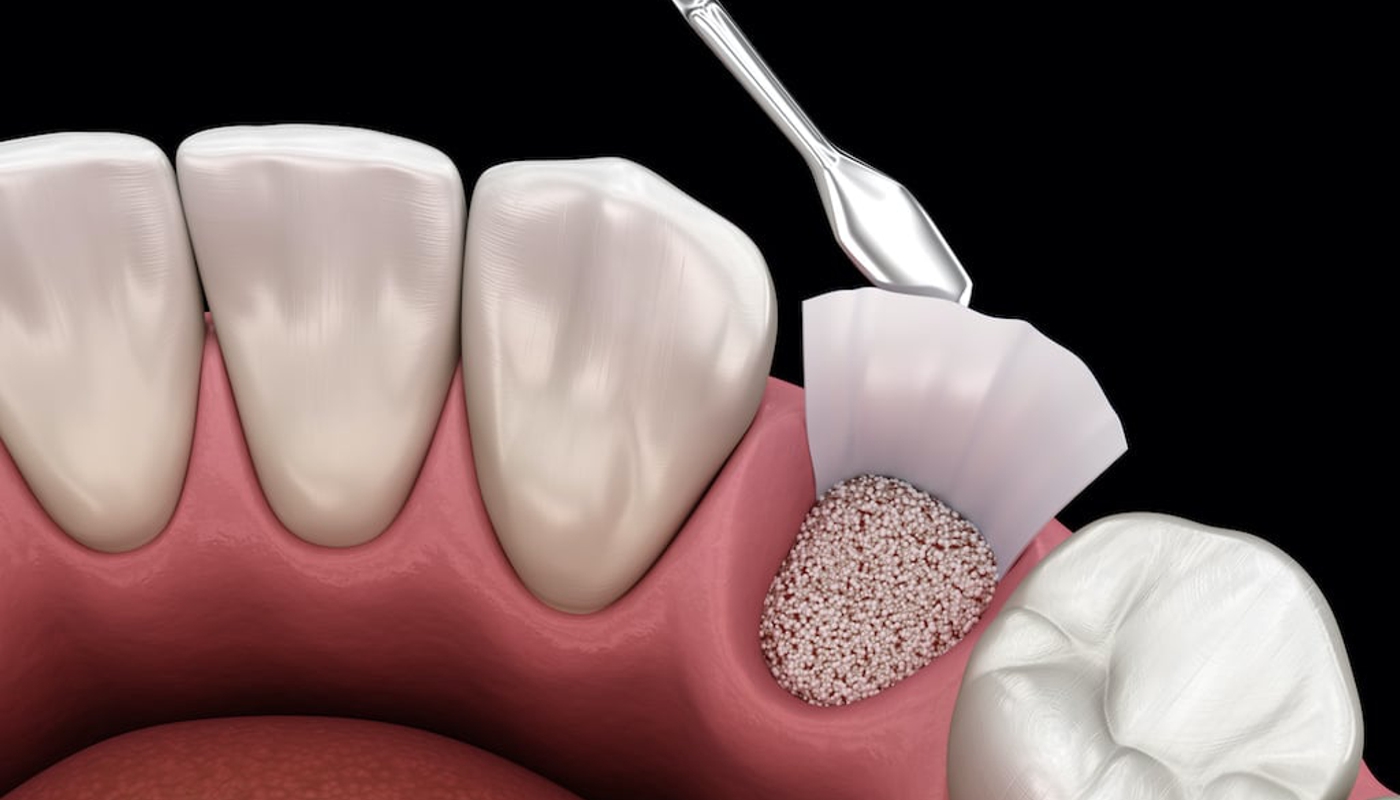

Rigenerazione ossea

La rigenerazione ossea è una tecnica avanzata che consente di ricostruire il tessuto osseo nei casi in cui non sia sufficiente per supportare un impianto dentale.